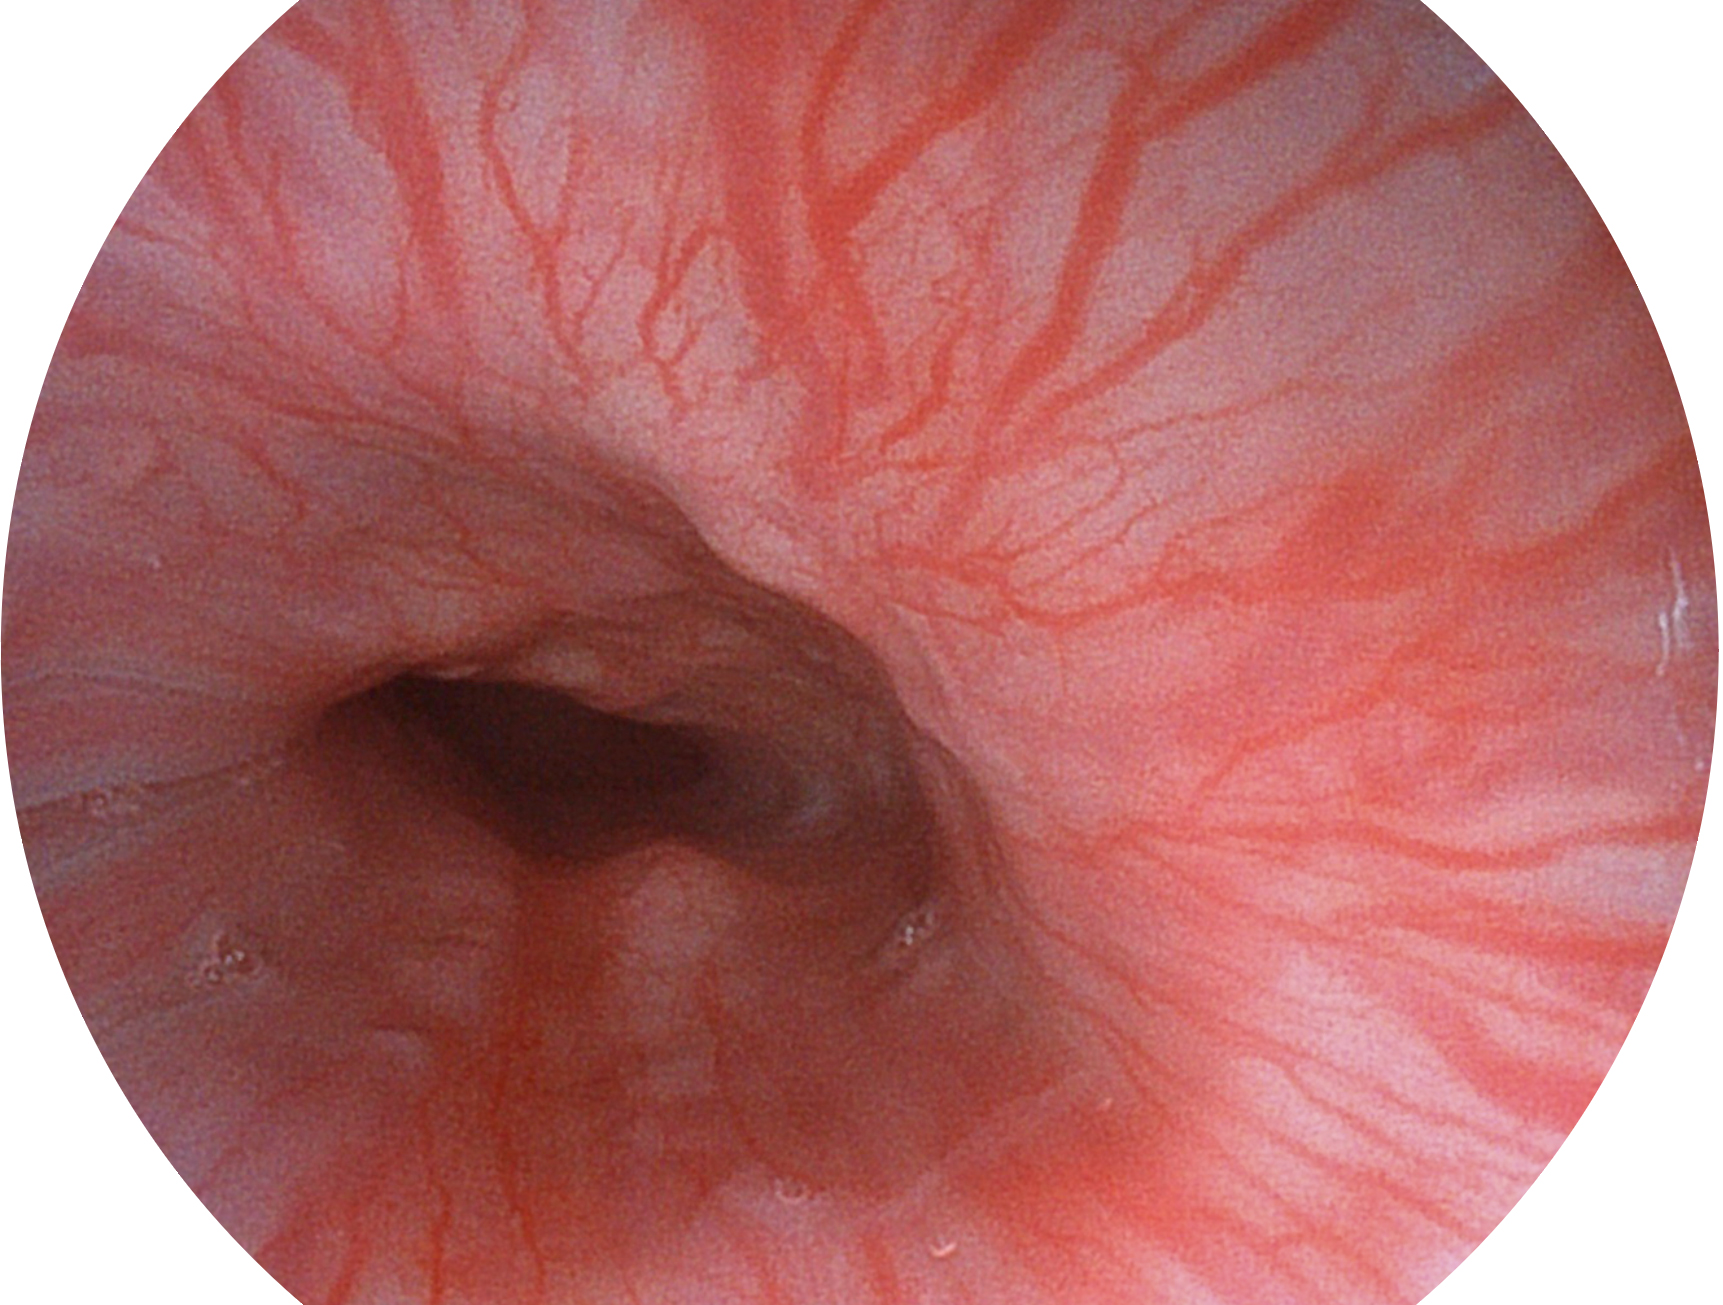

• 白光图像 SFI图像

SFI技术是结合特定光谱照明与数字光谱滤波,实现高亮度特殊光成像。染色模式下,不改变粘液、食物残渣、粪液等基本颜色,在保持与白光照明相似的图像色调的同时突显了图像颜色的红白对比度,且在远距离观察的情况下具备与普通白光模式相同的图像亮度,有助于消化道疾病的大范围扫查和早癌筛查。